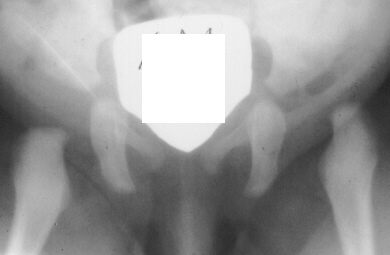

A ten year old female presented with a left hip dislocation. She was born by Cesarean-section because of slow progression of labor. The child was not breech and was noted to have a dislocatable hip at birth. There was a negative family history of DDH. An X-ray prior to application of the brace showed the dislocation of the hip. The patient was first seen at AIDI on 9th day. Abduction of the right hip was 80 degrees but left was only 60 degrees. There was a positive Galeazzi sign with the left hip being shorter than the right. X-rays showed a left hip dislocation and right hip subluxation . A Pavlik harness was applied. After two months, the right hip improved but the left hip was still dislocatable. For this, home traction was started. Even after 2 months, the left hip did not reduce. Therefore, an arthrogram, adductor tenotomy and closed reduction was done at 4 months of age. Single hip spica was applied with the hip in 40 abduction and 100 flexion. Eight weeks later an arthrogram was performed and the cast was reapplied with the hip in 35 degrees abduction and 100 degrees flexion.

Four months later, the spica cast was removed and an Atlanta brace was applied. X-rays showed avascular necrosis at ten months of age . At two years of age, the ossification of the left nucleus was still delayed. The leg lengths were equal and the range of motion of the hip was full.